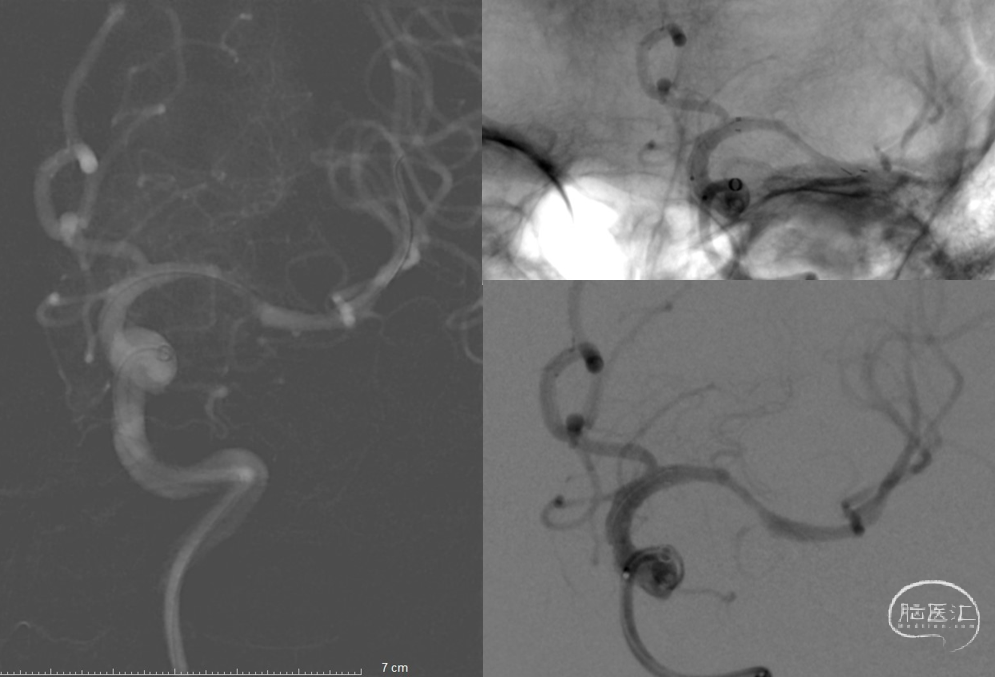

以泥鳅导丝携带8F Guiding及多功能造影管路图下同轴到颈内动脉,撤出多功能管。ASAHI-0.014in×200cm微导丝携带Navien-72及SL-10微导管到达颈内动脉末端,微导管造影再次证实大脑前动脉通畅,左侧大脑中动脉M1闭塞,微导丝通过闭塞段顺利证实为真腔,中间导管造影提示远端血流存在,前向血流缓慢,M1处重度狭窄,交换Transed 0.014in×300cm微导丝,经微导丝上Gateway 2.0mm×15mm球囊,与M1狭窄处行6ATM缓慢扩张,观察前向血流有所好转,于微导管处行替罗非班5ml缓慢注射接触性溶栓,观察5分钟,血管有所回弹。

ASAHI微导丝携带Navien-72及SL-10微导管,造影血管通畅,前向血流缓慢,给予Gateway 2.0mm×15mm球囊球扩

观察血管有所回弹,给予Gateway球囊以6ATM压力缓慢扩张,并缓慢注射替罗非班5ml

Neuroform Atlas 4.0mm×21mm支架释放满意